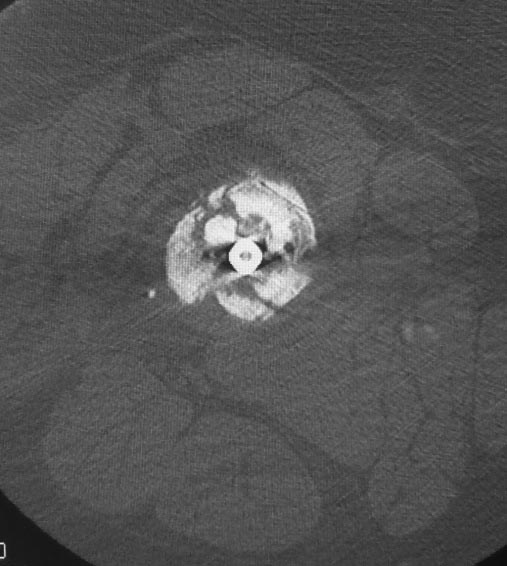

Уважаемые коллеги. Хотелось бы выслушать мнения и советы по представленному случаю. Пациент 42 лет, вес 130 кг, рост около 160 см, сахарный диабет в легкой форме (впервые выявлен после травмы). Травма в феврале 2011 г. - упал с мотоцикла на отдыхе за рубежом. По возвращении в Россию был прооперирован в несколько этапов: в марте 2011 г. - остеосинтез обеих костей правого предплечья пластинами по поводу открытого перелома; интрамедуллярный остеосинтез правого бедра; остеосинтез проксимального конца правой большеберцовой кости. В апреле 2011 г. был доставлен 1 блокирующий винт в дистальное отверстие гвоздя и выполнена пластика крестообразных и наружной боковой связок левого коленного сустава. В феврале 2012 г. были удалены фиксаторы с проксимального конца правой большеберцовой кости и выполнена пластика крестообразных и наружной боковой связок правого коленного сустава. За это время пациент смог начать ходить, сначала с костылями, а затем - без дополнительной опоры. Летом 2013 г. решил укрепить ноги с помощью подъемов пешком на пятый этаж. В результате - усталостная рефрактура правого бедра и перелом интрамедуллярного гвоздя. 09.09.2013 - реостеосинтез латеральным бедренным гвоздем с пластикой костной аутостружкой + СhronoS. Сейчас, через 6 мес после операции, может ходить без дополнительной опоры, периодически беспокоит болезненность в области правого бедра. На сегодняшних КТ - отсутствие признаков консолидации. Нужно ли что то делать и, если да, то что? Рассматриваемые варианты: повторная костная пластика дефекта; доставить блокирующие винты (самый проксимальный винт был удален через 3 мес после операции). Еще раз менять гвоздь не хотелось бы. На представленных снимках: бедро в 2011 г., через несколько мес после операции; в 2012 г., на стадии консолидации; со сломанным гвоздем; сразу после повторной операции (3 рентгенограммы). Все КТ - сегодняшние. Заранее спасибо за ответы.

Доброго дня! Уважаемый Сергей, думаю, что проблема не в необходимости костной пластики, а в отсутствии стабильной фиксации (как при инфраистмальном переломе большеберцовой кости).

ждать-не ждать? Срочности нет, подождать можно, но активно, т.е. оценить клиническую и рентгенологическую динамику: два месяца назад, сейчас и еще через пару месяцев. Уменьшатся боли, появится более убедительная мозоль - ждите и наблюдайте дальше. Отсутствие положительной динамики можно приравнять к отрицательной динамике. Очевидно, что здесь имеют место быть обе проблемы: биологическая -мозоль слабая и механическая - тонкий гвоздь, недостаточная стабильность. Тогда -удаление, рассверливание (очень аккуратное, по 0.5 мм шаг, острыми фрезами, чтобы не пожечь кость - кортикал толстый и довольно прочный). Для 130 кг диаметр гвоздя минимум 12 мм, лучше больше. Здесь можно и 14мм гвоздь взять и блокировать дистально винтами 6,0 мм. Открывать перелом и пытаться делать еще пластику экстрамедуллярно не стоит. Рассверливания будет достаточно.

Источник проблем - отсуствие рассверливания, тонкий гвоздь и костная пластика. При интрамедуллярном остеосинтезе (относительная стабильность) класть кусочки кости открыто бесполезно - не приживут. Только еще ухудшили кровоснабжение концов. А что там с длиной сегмента? Если длина не потерялась - реостеосинтез с рассверливанием, как А.Семенистый написал. Если укорочение - удалить, остеотомия на другом уровне и дистракиця, на стыке - компрессия, и по достижении нужной длины - заштифтовать с рассверливанием, аппарат снять только после запирания гвоздя.

При сопутствующей травме грудной клетки или при политравме допускается фиксация тонкими гвоздями с минимальным или без рассверливания канала. Тактика уменьшает second hit при damage control и стабилизирует перелом временно, но не гарантирует сращение. Рассверливание канала, кроме стабильности, создает экзотермическую температуру, которая улучшает ангиогенез за пределы канала, и поэтому происходит образование эндооссальной консолидации.

А открытая операция на диафизе приведет к ухудшению без того нарушенного кровоснабжения и не костная стружка, а широкий хирургический доступ приводит к нарушению кровоснабжения. При следующих процедурах желательно сохранить преимущество интактного кровобращения!!

Боли в области ложного сустава подтверждают, что ожидания не помогут и приведут к повторному перелому интрамедуллярного гвоздя. Стандартная процедура - рассверливание и толстый гвоздь в динамике. Нагрузка с первых дней.